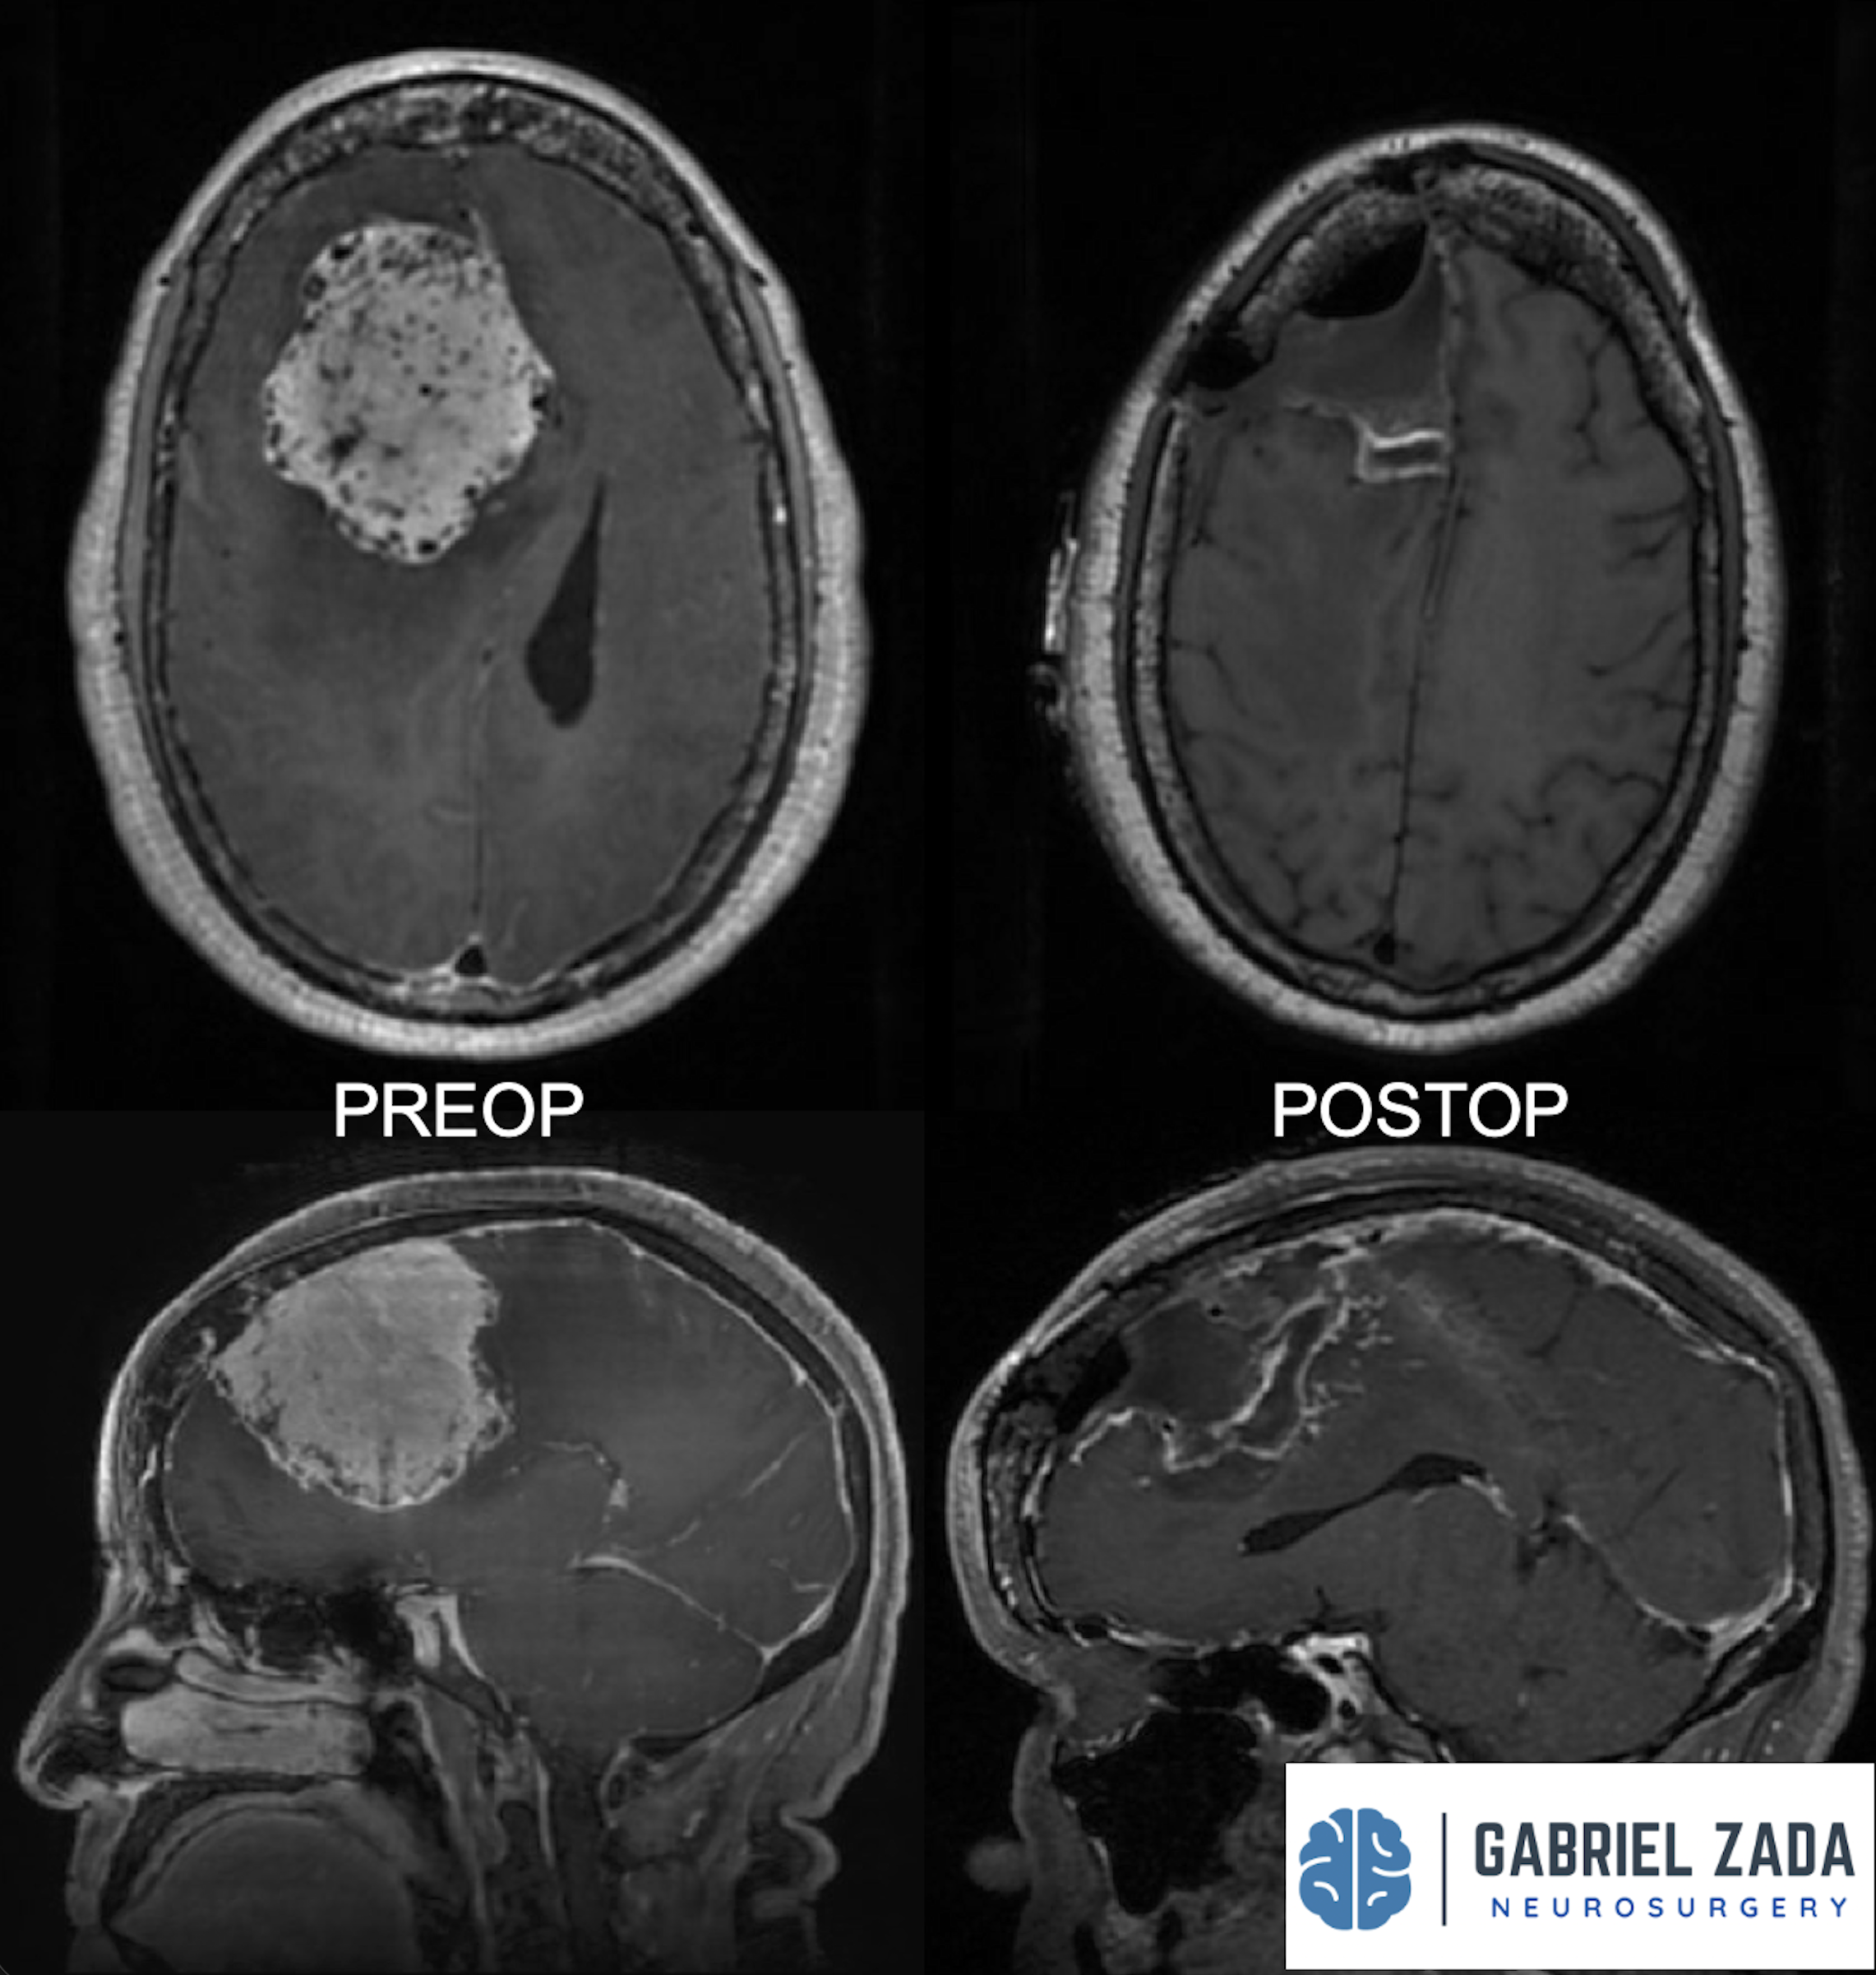

Explore this comprehensive gallery featuring pre‑ and post‑operative imaging of patients with skull‑base tumors treated by Gabriel Zada, MD, MS, FAANS, FACS. These cases highlight Dr. Zada’s expertise in advanced neurosurgical techniques and outcomes.

*Representative cases shown for educational purposes. All images de-identified. Individual results vary.